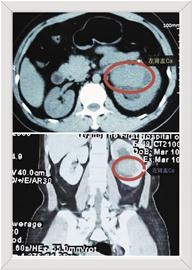

术前CT平扫及增强显示左肾盂占位。

患者康某,49岁。因左侧腰腹部疼痛不适已达3天,在当地医院检查初诊为左侧肾盂占位病变,病变部位大小约73*44*55毫米。康某及其家属为进一步查明病因,来到益阳市第一中医医院复诊。当值医生泌尿外科主任曾立瑛仔细询问病史,并查看初诊结果后考虑“左侧肾盂癌”的可能性大,建议住院进行手术治疗。

入院后,曾立瑛立即为患者进行了全面检查。泌尿系增强CT提示:左侧肾盂占位。复诊结果无误。